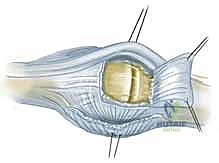

قبل الخوض في التفاصيل التقنية للإجراء الجراحي، من الضروري والمحوري أن نفهم البنية التشريحية المعقدة لمفصل MCP. هذا المفصل هو الرابط الحيوي بين عظام راحة اليد (الأمشاط - Metacarpals) وعظام الأصابع الأولى (السلاميات القريبة - Proximal Phalanges). يُصنف هذا المفصل على أنه مفصل لقمي (Condyloid Joint)، مما يعني أنه يسمح بحركات متعددة في مستويات مختلفة: الثني (Flexion)، البسط (Extension)، الانحراف الزندي (Ulnar Deviation)، الانحراف الكعبري (Radial Deviation)، بالإضافة إلى الحركة الدائرية المحدودة (Circumduction).

- وتر الباسطة الرقمية المشتركة (Extensor Digitorum Communis - EDC): هو اللاعب المركزي والنجم في إجراء اليوم الجراحي. يتم الاحتفاظ بهذا الوتر في المنتصف تماماً فوق قمة مفصل MCP بواسطة هياكل تُعرف بـ الأربطة السهمية (Sagittal Bands).

- الأربطة السهمية: هي ألياف مستعرضة قوية تنشأ من غطاء الباسطة (Extensor Hood) وتتصل من الناحية الراحية بالصفيحة الراحية والرباط بين الأمشاط المستعرض، لتشكل آلية تشبه "الحبال" أو "المقلاع" (Sling mechanism) تحافظ على الوتر في مكانه. يُعتبر الرباط السهمي الزندي عموماً أقوى وأكثر كثافة من نظيره الكعبري، وهو عامل بيوميكانيكي يساهم في سهولة انزلاق الوتر نحو الجهة الزندية (Ulnar Subluxation) عندما يضعف الرباط الكعبري بسبب المرض.

- تمزق الرباط السهمي الكعبري (Radial Sagittal Band Attenuation): التورم المستمر يضغط على الأربطة السهمية التي تثبت الوتر الباسط. نظراً لأن الرباط الكعبري أضعف بطبيعته، فإنه يتمدد أو يتمزق أولاً.

- الانزلاق الزندي للوتر الباسط (Ulnar Subluxation of EDC): بمجرد ضعف الرباط السهمي الكعبري، ينزلق وتر الباسطة (EDC) من أعلى قمة المفصل نحو الوادي الزندي بين الأمشاط. عندما يحدث هذا، يفقد الوتر قدرته على بسط الإصبع بفعالية، وبدلاً من ذلك، تصبح قوة سحبه مساهمة في زيادة الانحراف الزندي للأصابع.